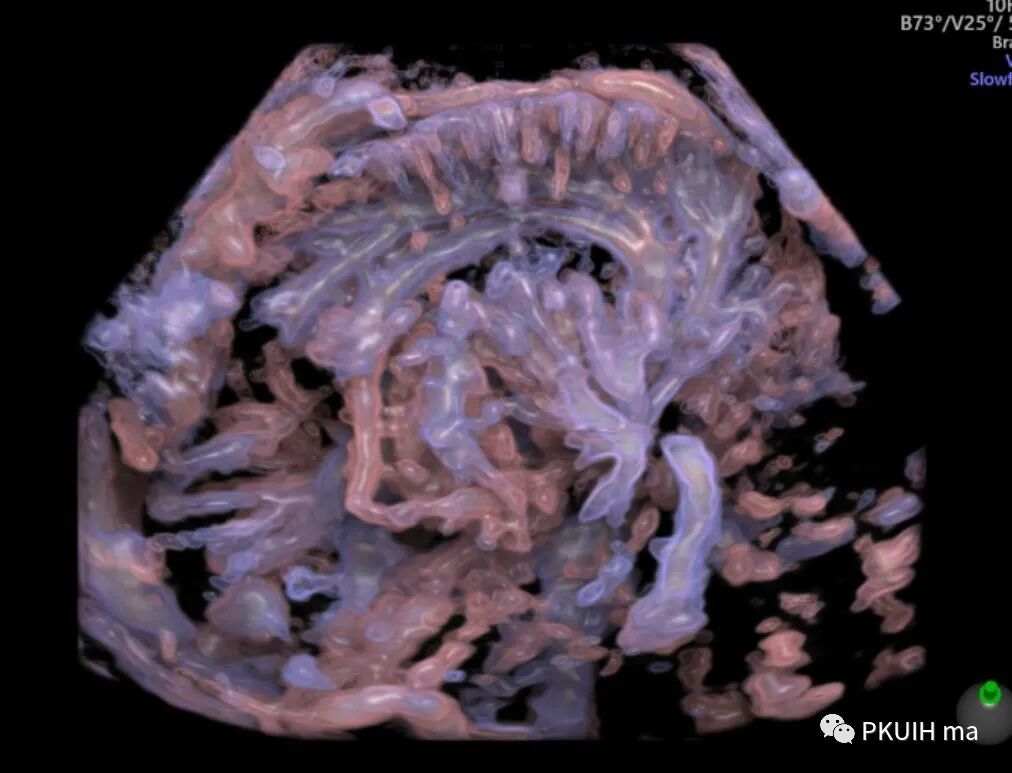

同样我们可以利用容积血流成像来显示颅底动脉环,看着更有立体感,但效果不如SlowFlow功能